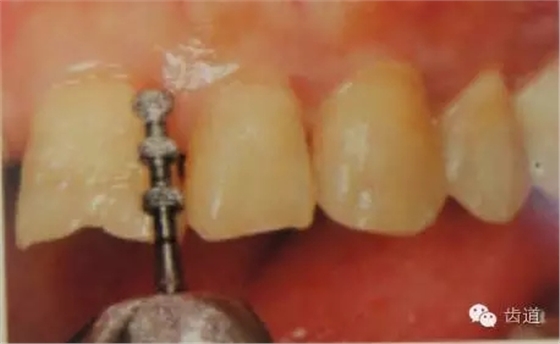

1、唇面預(yù)備:先用定深車針定出定深溝,再換合適車針磨除剩余的釉質(zhì)。

唇面磨除的量依據(jù)所用貼面材料及牙齒的變色程度而定。

如下圖:

預(yù)備齦下邊緣之前要先排齦,之后選用圓頭錐形車針磨除牙體到所設(shè)計(jì)的邊緣位置。

1)排齦

2)制備